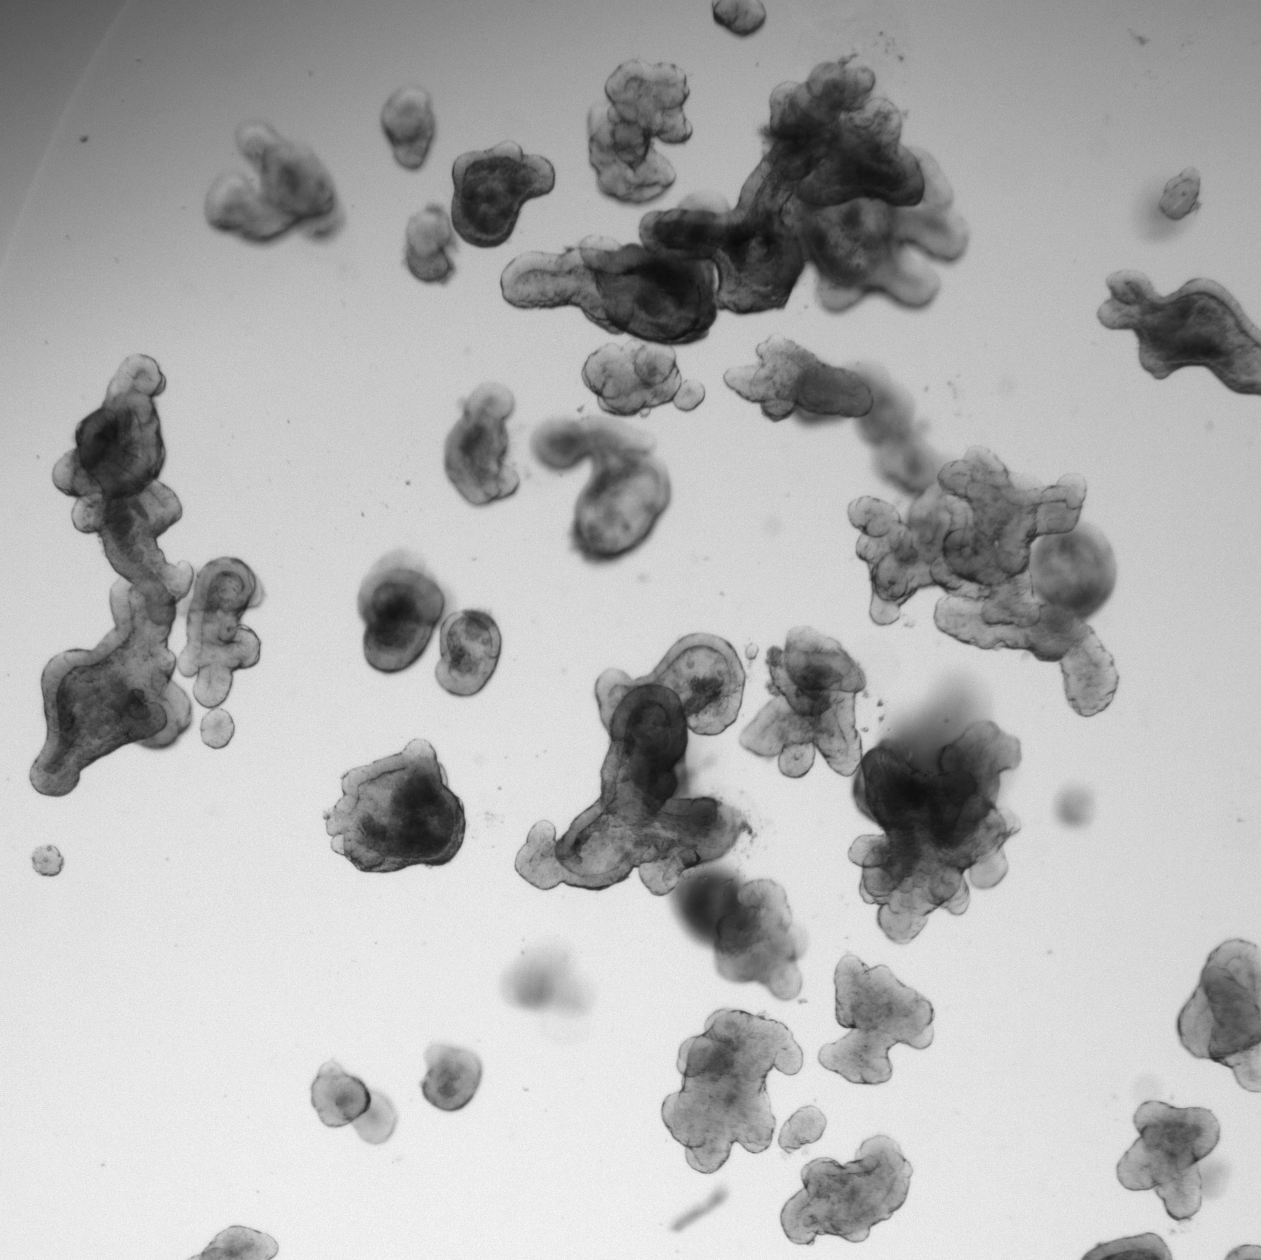

"We knew that these types of tumors mainly respond to a combination of drugs, but not exactly why," Hugo explains. "With our Oncode base funding, we were able to invest in developing a very sensitive and precise measurement system: a microscopic technique that allows us to zoom in on individual cells and also to film over time how well these cells respond to treatments." Using the mini-tumors, the team shows in their paper that inhibiting signaling pathways in cells did not happen with a single therapy, but required a combination. "This is because we need to dampen these signaling pathways much harder than thought, and then we could measure before. Thanks to our precise measurement method, we now understand that there is a self-reinforcing mechanism in the signaling pathway and that you therefore have to push more than one button to sufficiently inhibit the sometimes complex signaling pathways to fight the tumor," explains Bas Ponsioen, post-doctoral researcher in the lab of Hugo and the leading author of the paper.